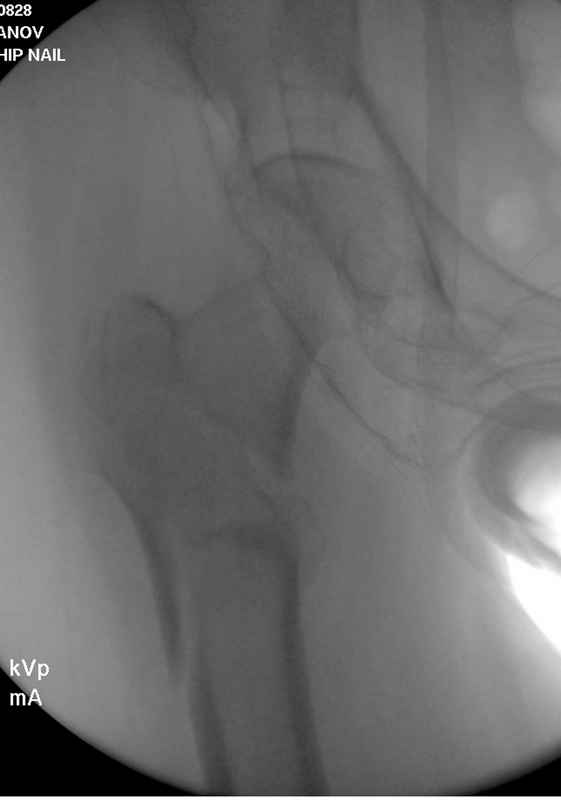

Здесь 83 года, травма в результате падения

Djoldas Kuldjanov, M.D.

Department of Orthopedic Surgery

St. Louis University